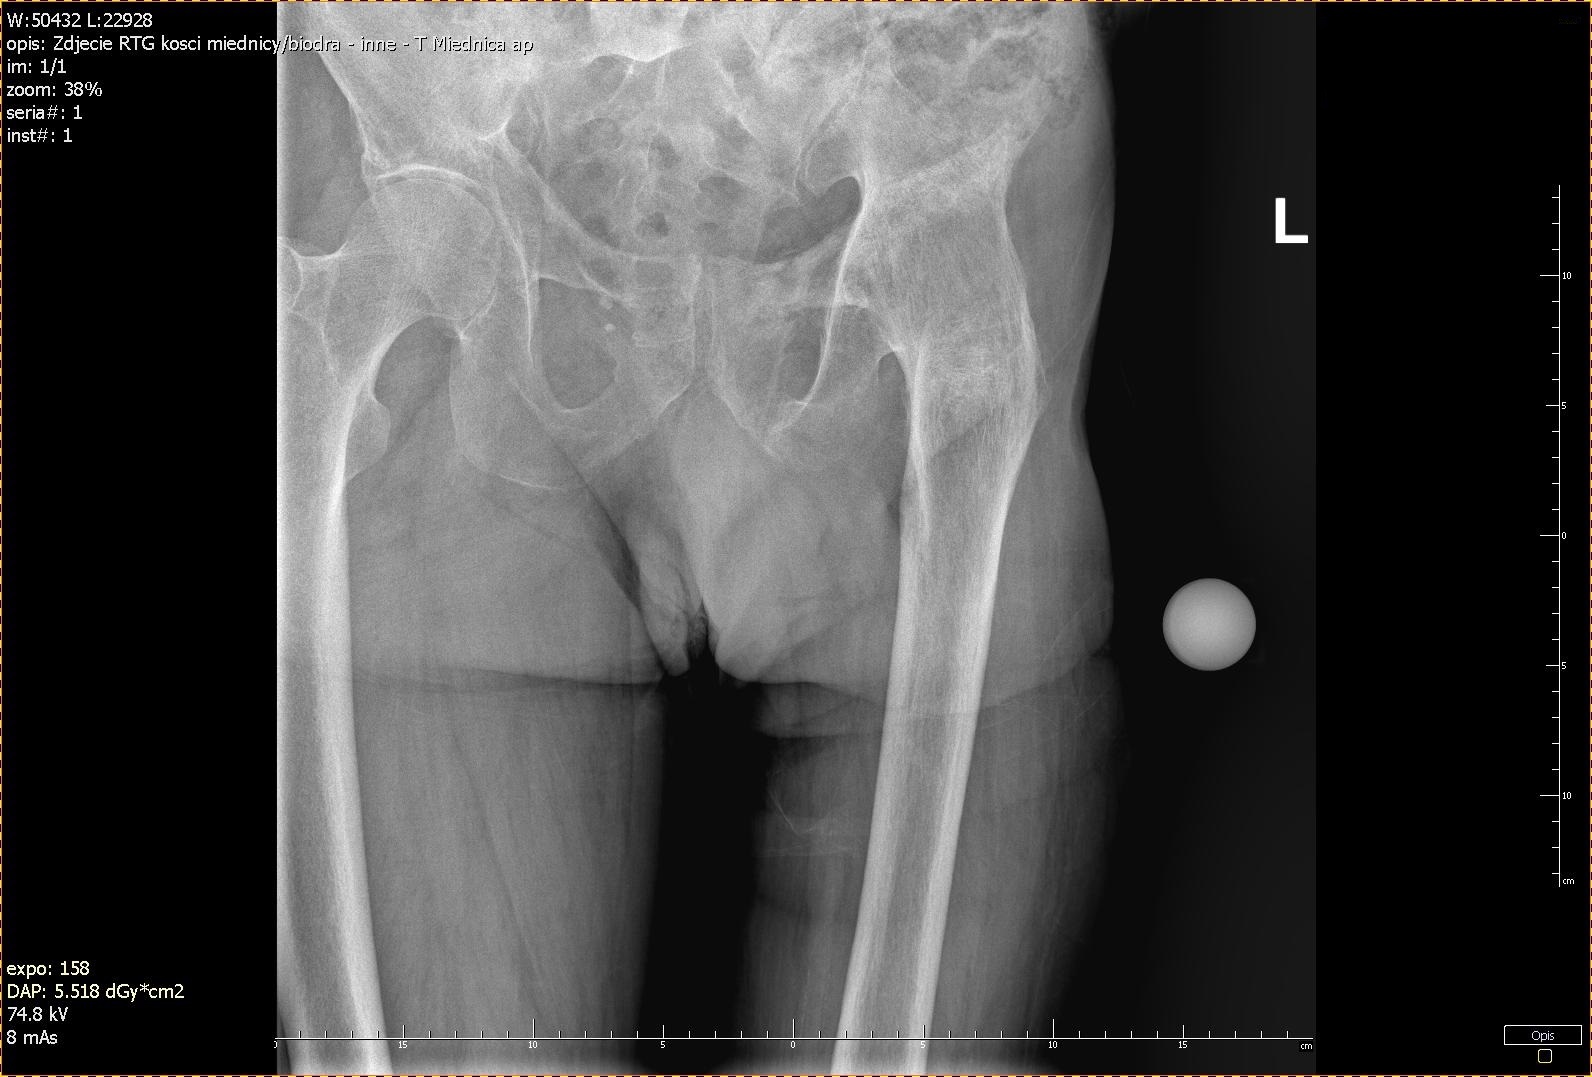

A 70-year-old male presented in the Orthopedics Clinic on the 25th of April 2019, with debilitating pain in the left knee. Apart from limitations in his daily activities, the patient complained about difficulties in driving a car, walking longer distances above 1km, excluding him from recreational activities. The patient had tuberculosis at a young age, which led to the spontaneous fusion of his left hip. On physical examination, the hip was immobile, fused in 10◦ flexions, 0° rotation, and 5° abduction, with no movement in the joint. The left knee had limited mobility to 70° flexion, and flexion contracture of 8° was present, as well as positive Solo-Halla’s and Zohlen’s signs and a sense of friction was felt during the knee movements. Leg length discrepancy measured 3 cm. The strength of the muscles surrounding the hip was evaluated according to Lovett’s scale: flexion - 3; extension - 2; internal and external rotation - both 1.

The [computed tomography (CT)] scan of the lower limbs revealed generalized osteoporotic changes, left hip ankylosis, past fracture of pelvic bones (partial union of the left side of the sacral bone, and a non-union of the upper and lower branch of the pubic bone), atrophy of lower limb girdle’s muscles on the left side, and also considerable degenerative changes in the lumbar spine, non-significant degenerative changes in the right hip joint and focal osteolysis in the sacral bone on the right side – indicative of a brown tumor, which was related to chronic kidney failure as well as generalized osteoporotic changes.

Several reports were published to discuss the results of patients with combined fusion conversion to THR and TKA (including bilateral surgery).3,8,9 In a series of Romness et al., 12/16 patients with fusion takedown with THR and TKA performed later with a mean follow-up of 5,5 years, patients with THR had a slightly lower range of motion postoperatively than patients with TKA alone (3-72 vs. 0-83), but both groups showed similar improvement of HSS knee score (from 28 to 72,2 and 43,5 to 72,1 respectively). However, the authors mention that the group with conversion to THR before knee replacement had more advanced arthritic changes in the knee, as evidenced on radiographs.8 The authors also stated that the numbers are too small to conclude that TKA alone is superior to a combination of THR and TKA. This is particularly important because in another study by Rittmeister et al. contradictory results were reported, and in his series, patients with TKA alone had poorer outcomes.9 Taking all of the factors described above into account, as well as the individual features of our patient, such as good abductor muscles, state on palpation, the advancement of knee joint degeneration evidenced on CT and by X-ray, and his overall condition - despite ESRD which was well controlled in his case - he was concerned a good candidate for both conversion to THR and knee replacement surgery.